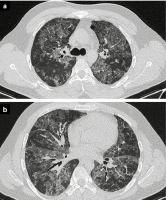

Thorax-CT

Abbildung 4a-b: Thorax-CT-Befund. Es finden sich im Bereich beider Lungen ohne basoapikalen Gradienten fleckigkonfluierende, lobuläre Areale an Milchglastrübungen sowie betonte Intralobulär- und Interlobulärsepten im Sinne eines „crazy paving“. Der Lungenkern ist tendenziell stärker von den Veränderungen betroffen, die unmittelbare subpleurale Lunge ist teilweise ausgespart bzw. geringer betroffen. Soweit nativmorphologisch beurteilbar kein Nachweis pathologisch vergrößerter mediastinaler, hilärer oder axillärer Lymphknoten. Die Pleura stellt sich nativ morphologisch unauffällig dar. Kein Pleuraerguss.

Keywords: CTThorax